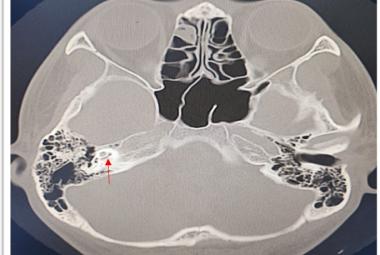

Labyrinthitis Ossificans Post COVID Vaccination